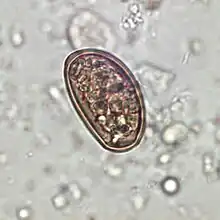

Dicrocoelium dendriticum egg in an unstained stool wet mount slide

Traditionally, diagnosis for dicrocoeliasis infection involves the identification of Dicrocoelium dendriticum eggs in the faeces of a human or other animal. However, in humans, eggs in the stool may be a result of ingesting raw infected animal liver and may not in fact indicate dicrocoeliasis.[9] Therefore, examining bile or duodenal fluid for eggs is a more accurate diagnostic technique in combination with a liver-free diet.[6]